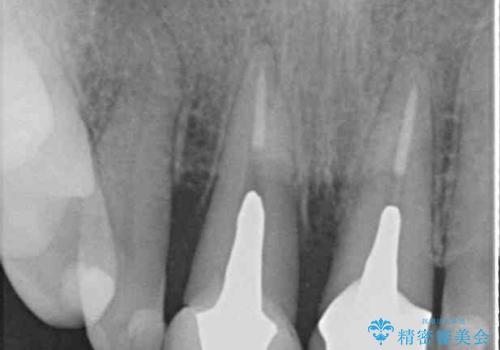

- 神経の抜いた歯が折れてしまい、痛みを感じて来院された患者様です。

折れてしまった歯は抜歯せざるを得ないため、抜歯と同時に仮歯を装着し、その後オールセラミックブリッジにて補綴することとしました。

折れた前歯を抜歯すると、歯肉が痩せてしまい、ブリッジの形態の審美性が失われることがあります。仮歯を調整することで審美回復が必要であるか判断しますが、今回は歯肉移植を行うことなく補綴治療を行いました。